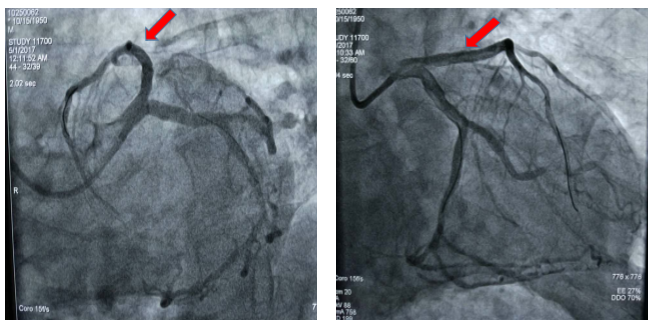

图1 患者术前冠脉造影显示冠脉血管前降支近段100%闭塞